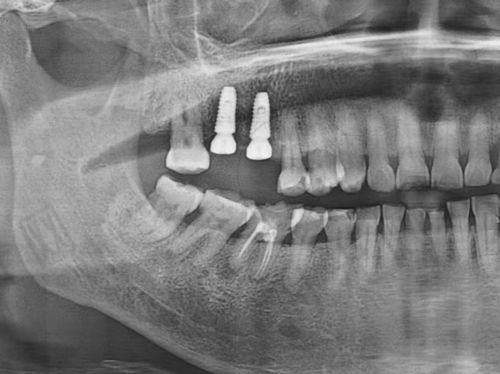

种牙就像盖房子,牙槽骨是“地基”,必须够结实。医生会用CT检查骨头的高度和宽度:高度至少要10mm,宽度至少4mm(大约一根手指的厚度)。如果骨头太“瘦”或有缺损,就像地基不牢,种进去的牙可能会松动。

举个例子:28岁的小李因蛀牙拔掉了molar(后槽牙),CT显示牙槽骨高度11mm、宽度5mm,没有炎症,医生当天就给他种了国产创英种植体,手术半小时完成。而65岁的张阿姨因为牙周病掉牙,牙槽骨吸收到只剩6mm,只能先做骨增量手术,等3个月骨头长好再种牙。